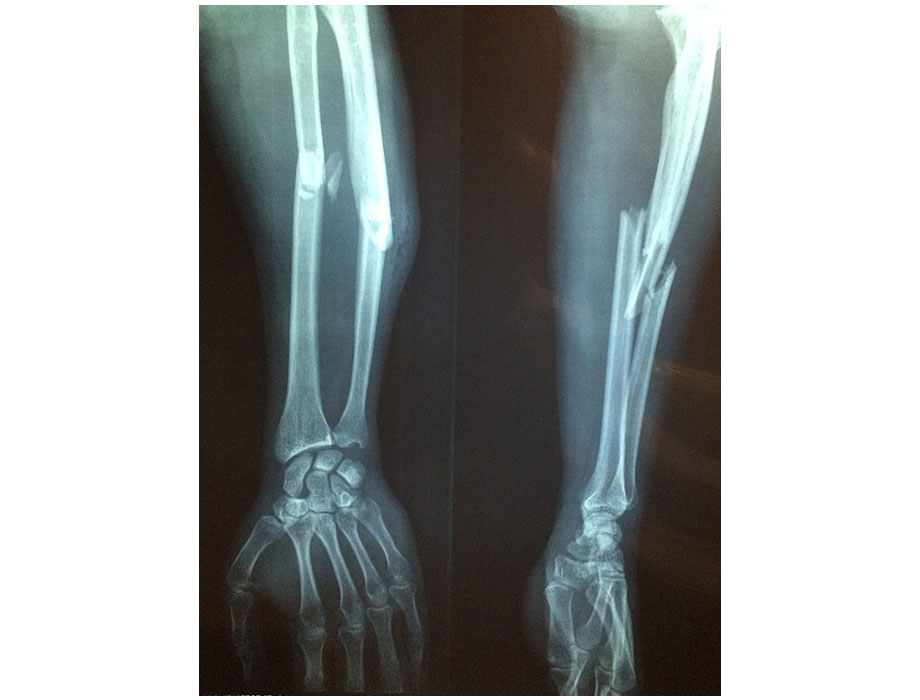

Más allá de la estadística general, hay un grupo particularmente vulnerable: las personas con discapacidad y movilidad reducida. Esta enfermedad debilita los huesos al reducir su densidad y calidad, volviéndolos frágiles y propensos a fracturas, en especial en la cadera, la columna y la muñeca. “Lo más grave es que avanza sin síntomas claros y muchas veces se descubre hasta que ocurre la primera fractura. La osteoporosis deteriora la estructura interna del hueso, lo hace más poroso y menos resistente, como si se debilitara desde adentro. Por eso puede fracturarse con movimientos mínimos”, comentó Arturo Pichardo, médico cirujano especialista en rehabilitación.

Esta fragilidad es todavía más evidente en quienes no pueden mantenerse activos, ya que la falta de movimiento acelera la pérdida de masa ósea. Los huesos, al igual que los músculos, necesitan estímulos mecánicos para conservar su densidad. Cuando una persona permanece en cama, en silla de ruedas o con movilidad muy limitada por enfermedades neurológicas como el Parkinson, la esclerosis múltiple o un infarto cerebral (EVC), el deterioro óseo se acelera.